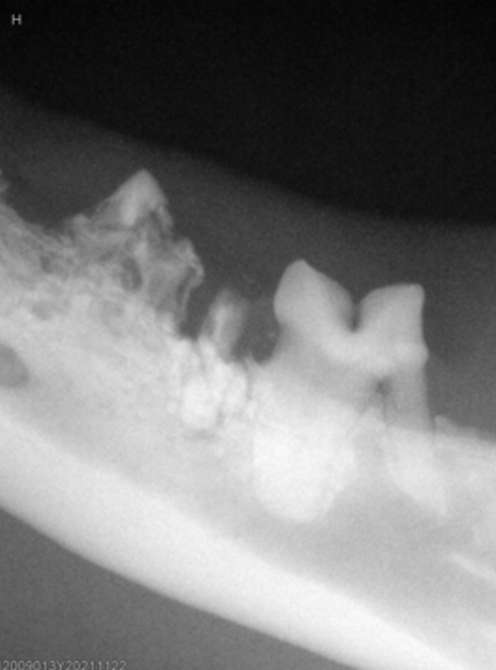

動物牙科X光機使用時機3:牙髓(根管)疾病治療

許多動物在日常生活中常會去啃咬像骨頭、木頭、家具、較硬的玩具或球類等物品,這些行為都可能使牙齒受到過度磨損,甚至是斷裂,而牙髓裸露的情況就有機會隨之發生,需要進一步進行「牙髓(根管)疾病治療」。

全球小動物獸醫協會發布的準則顯示(註3),49.6 %的動物都有「牙齒折斷」的經驗,其中更有10%的狗狗發生過至少1顆以上的牙齒,有牙髓裸露的情況,而裸露後若造成牙髓感染發炎,很多時候光看表面是無法察覺異狀的!

以動物的習性而言,顯少表現出任何明顯的臨床症狀,所以在診斷或確定治療前,動物很可能早就飽受長時間的牙疼問題,故在外在表徵不太明顯的情況下,使用牙科X光機拍攝,即可直覺性地協助獸醫師經準判斷治療方式。

圖片來源:https://www.montanapetdental.com/periapical-lucencies/